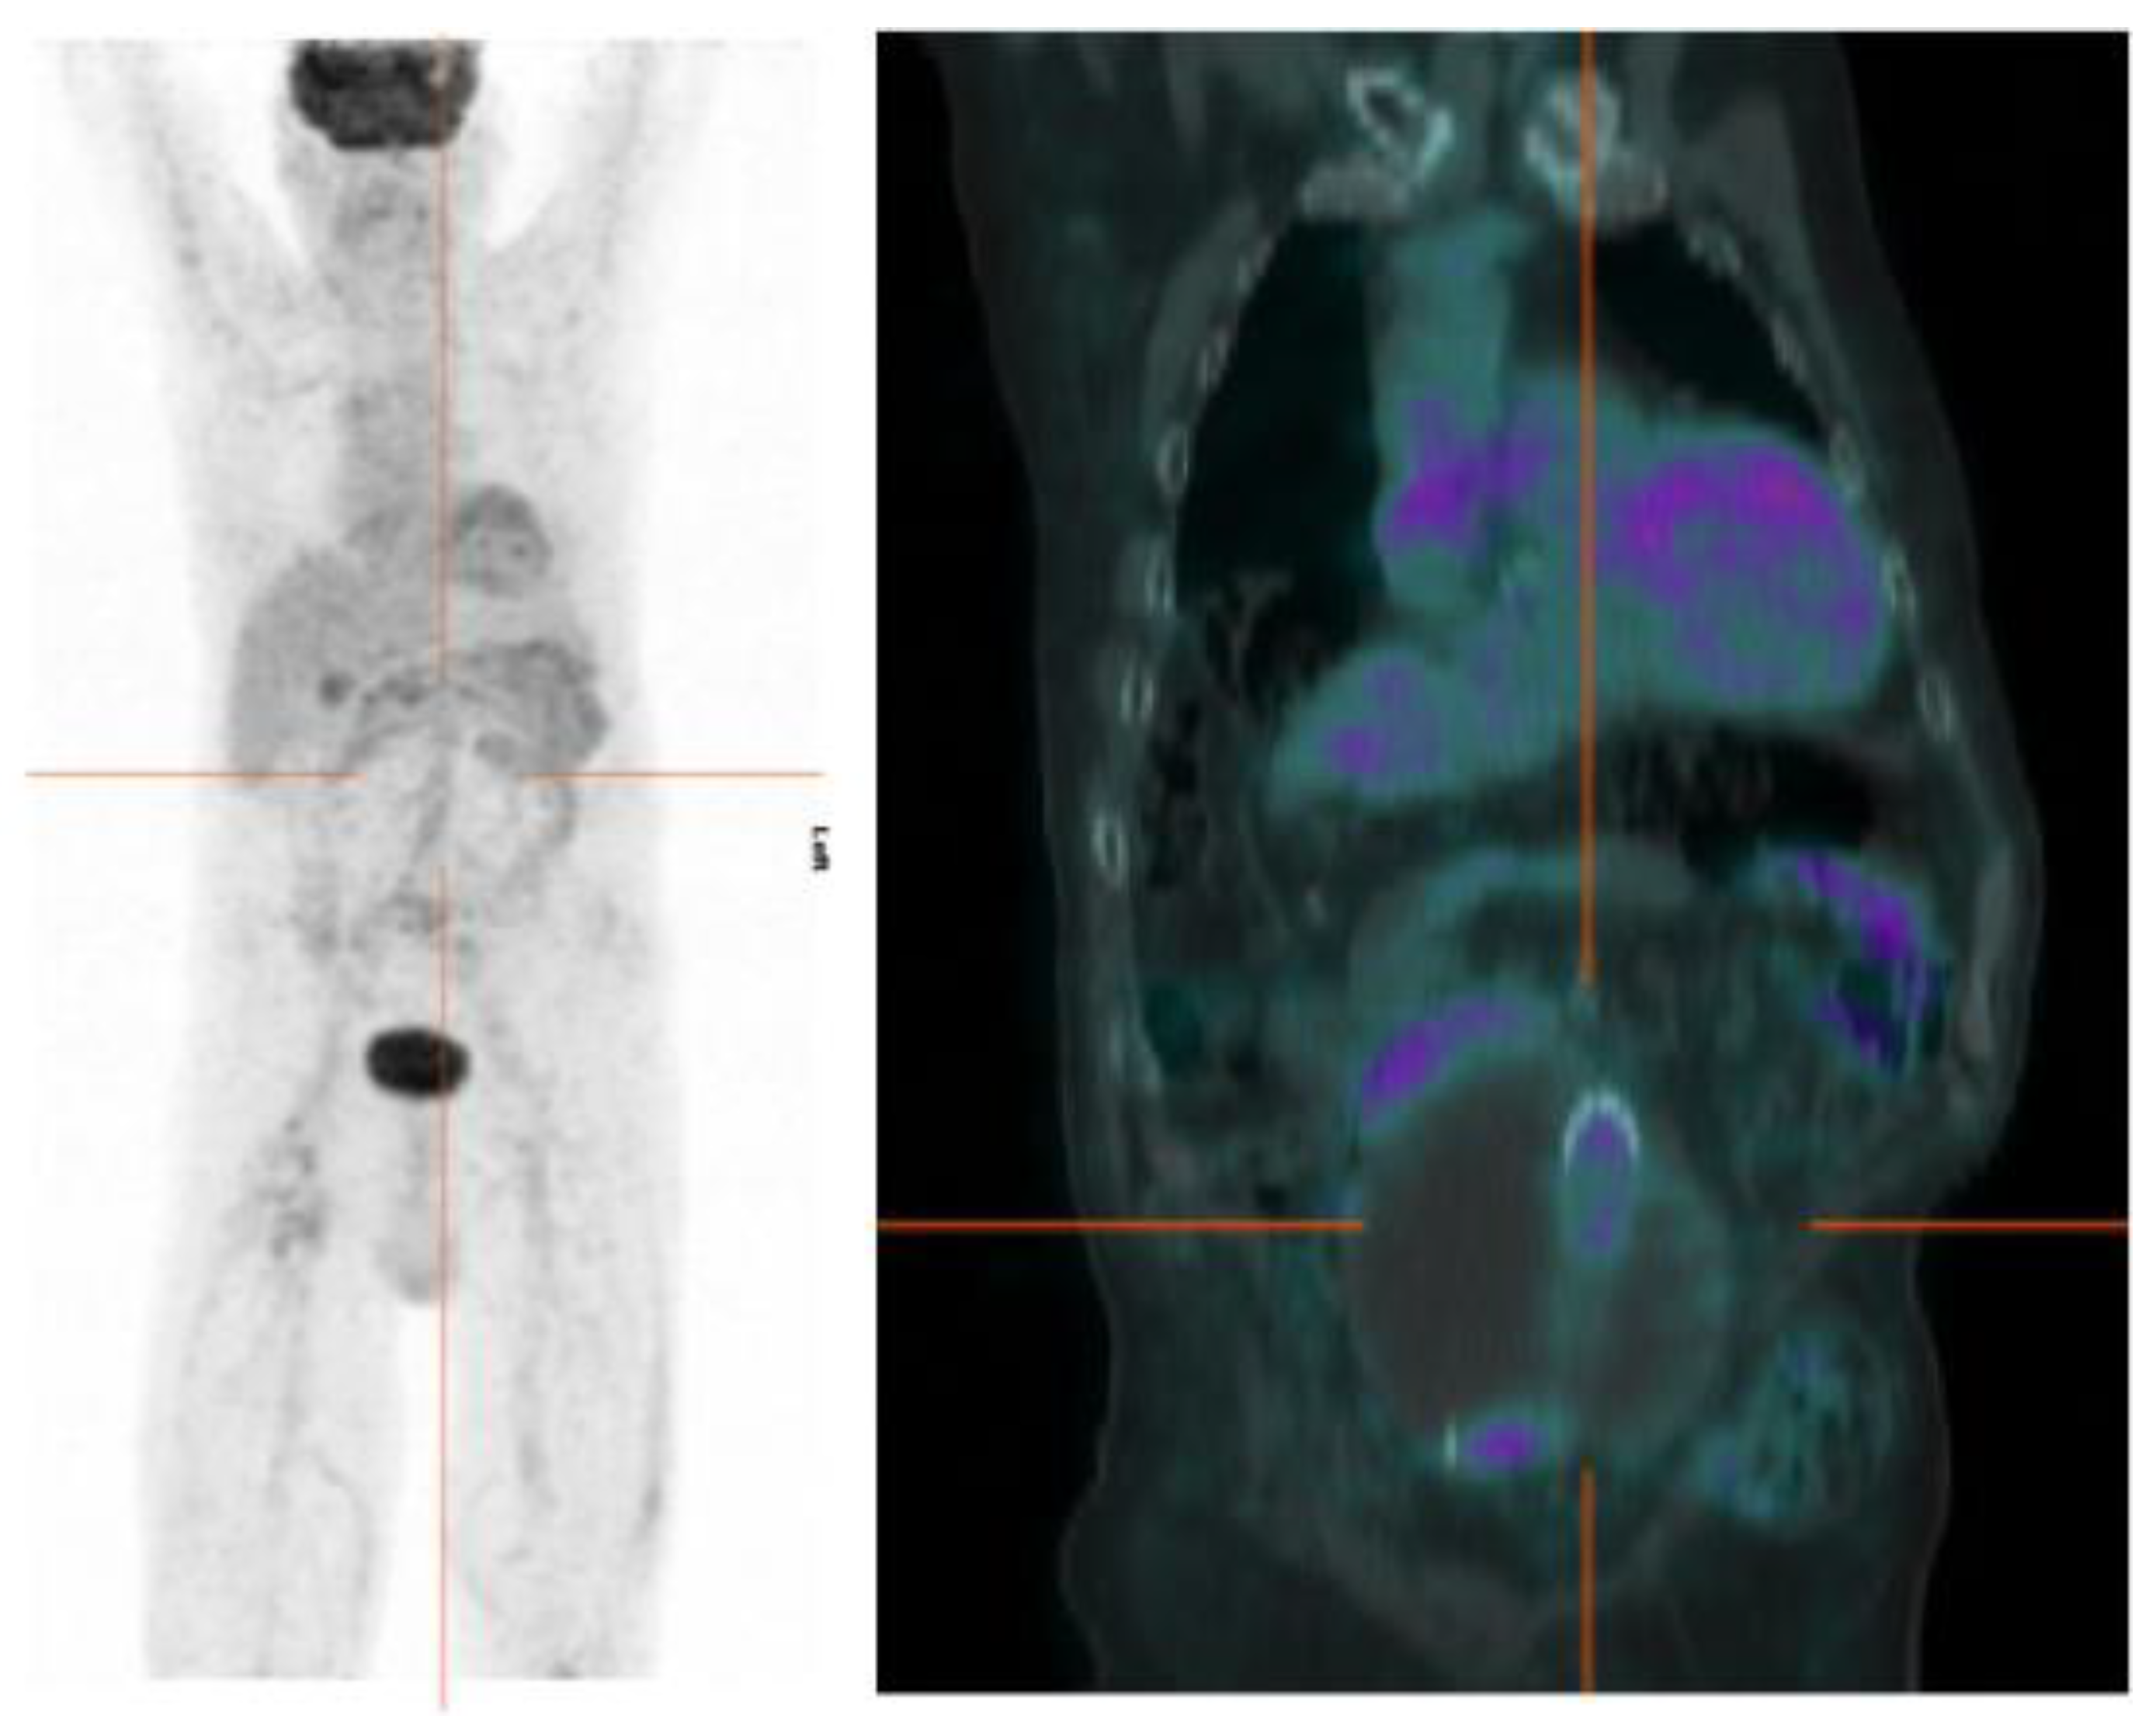

4.2. [18F]FDG PET/CT Imaging of VGI